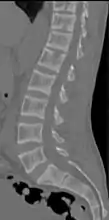

Renal osteodystrophy is usually diagnosed after treatment for end-stage kidney disease begins; however the CKD-MBD starts early in the course of CKD.[1][6] In advanced stages, blood tests will indicate decreased calcium and calcitriol (vitamin D) and increased phosphate, and parathyroid hormone levels. In earlier stages, serum calcium, phosphate levels are normal at the expense of high parathyroid hormone and fibroblast growth factor-23 levels. X-rays will also show bone features of renal osteodystrophy (subperiostic bone resorption, chondrocalcinosis at the knees and pubic symphysis, osteopenia and bone fractures) but may be difficult to differentiate from other conditions. Since the diagnosis of these bone abnormalities cannot be obtained correctly by current clinical, biochemical, and imaging methods (including measurement of bone-mineral density), bone biopsy has been, and still remains, the gold standard analysis for assessing the exact type of renal osteodystrophy.[6][16]

18. 1 2 3 4 5 6 7 Patel, Anish A.; Ramanathan, Rohit; Kuban, Joshua; Willis, Marc H. (2015). "Imaging Findings and Evaluation of Metabolic Bone Disease". Advances in Radiology. 2015: 1–21. doi:10.1155/2015/812794. ISSN 2356-6876.